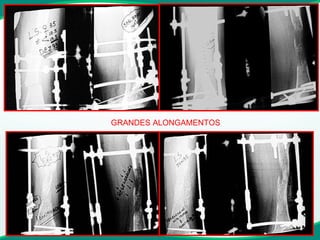

GRANDES ALONGAMENTOS

ALONGAMENTO 13 cm, DEVE SER FEITO ?? GRANDES ALONGAMENTOS